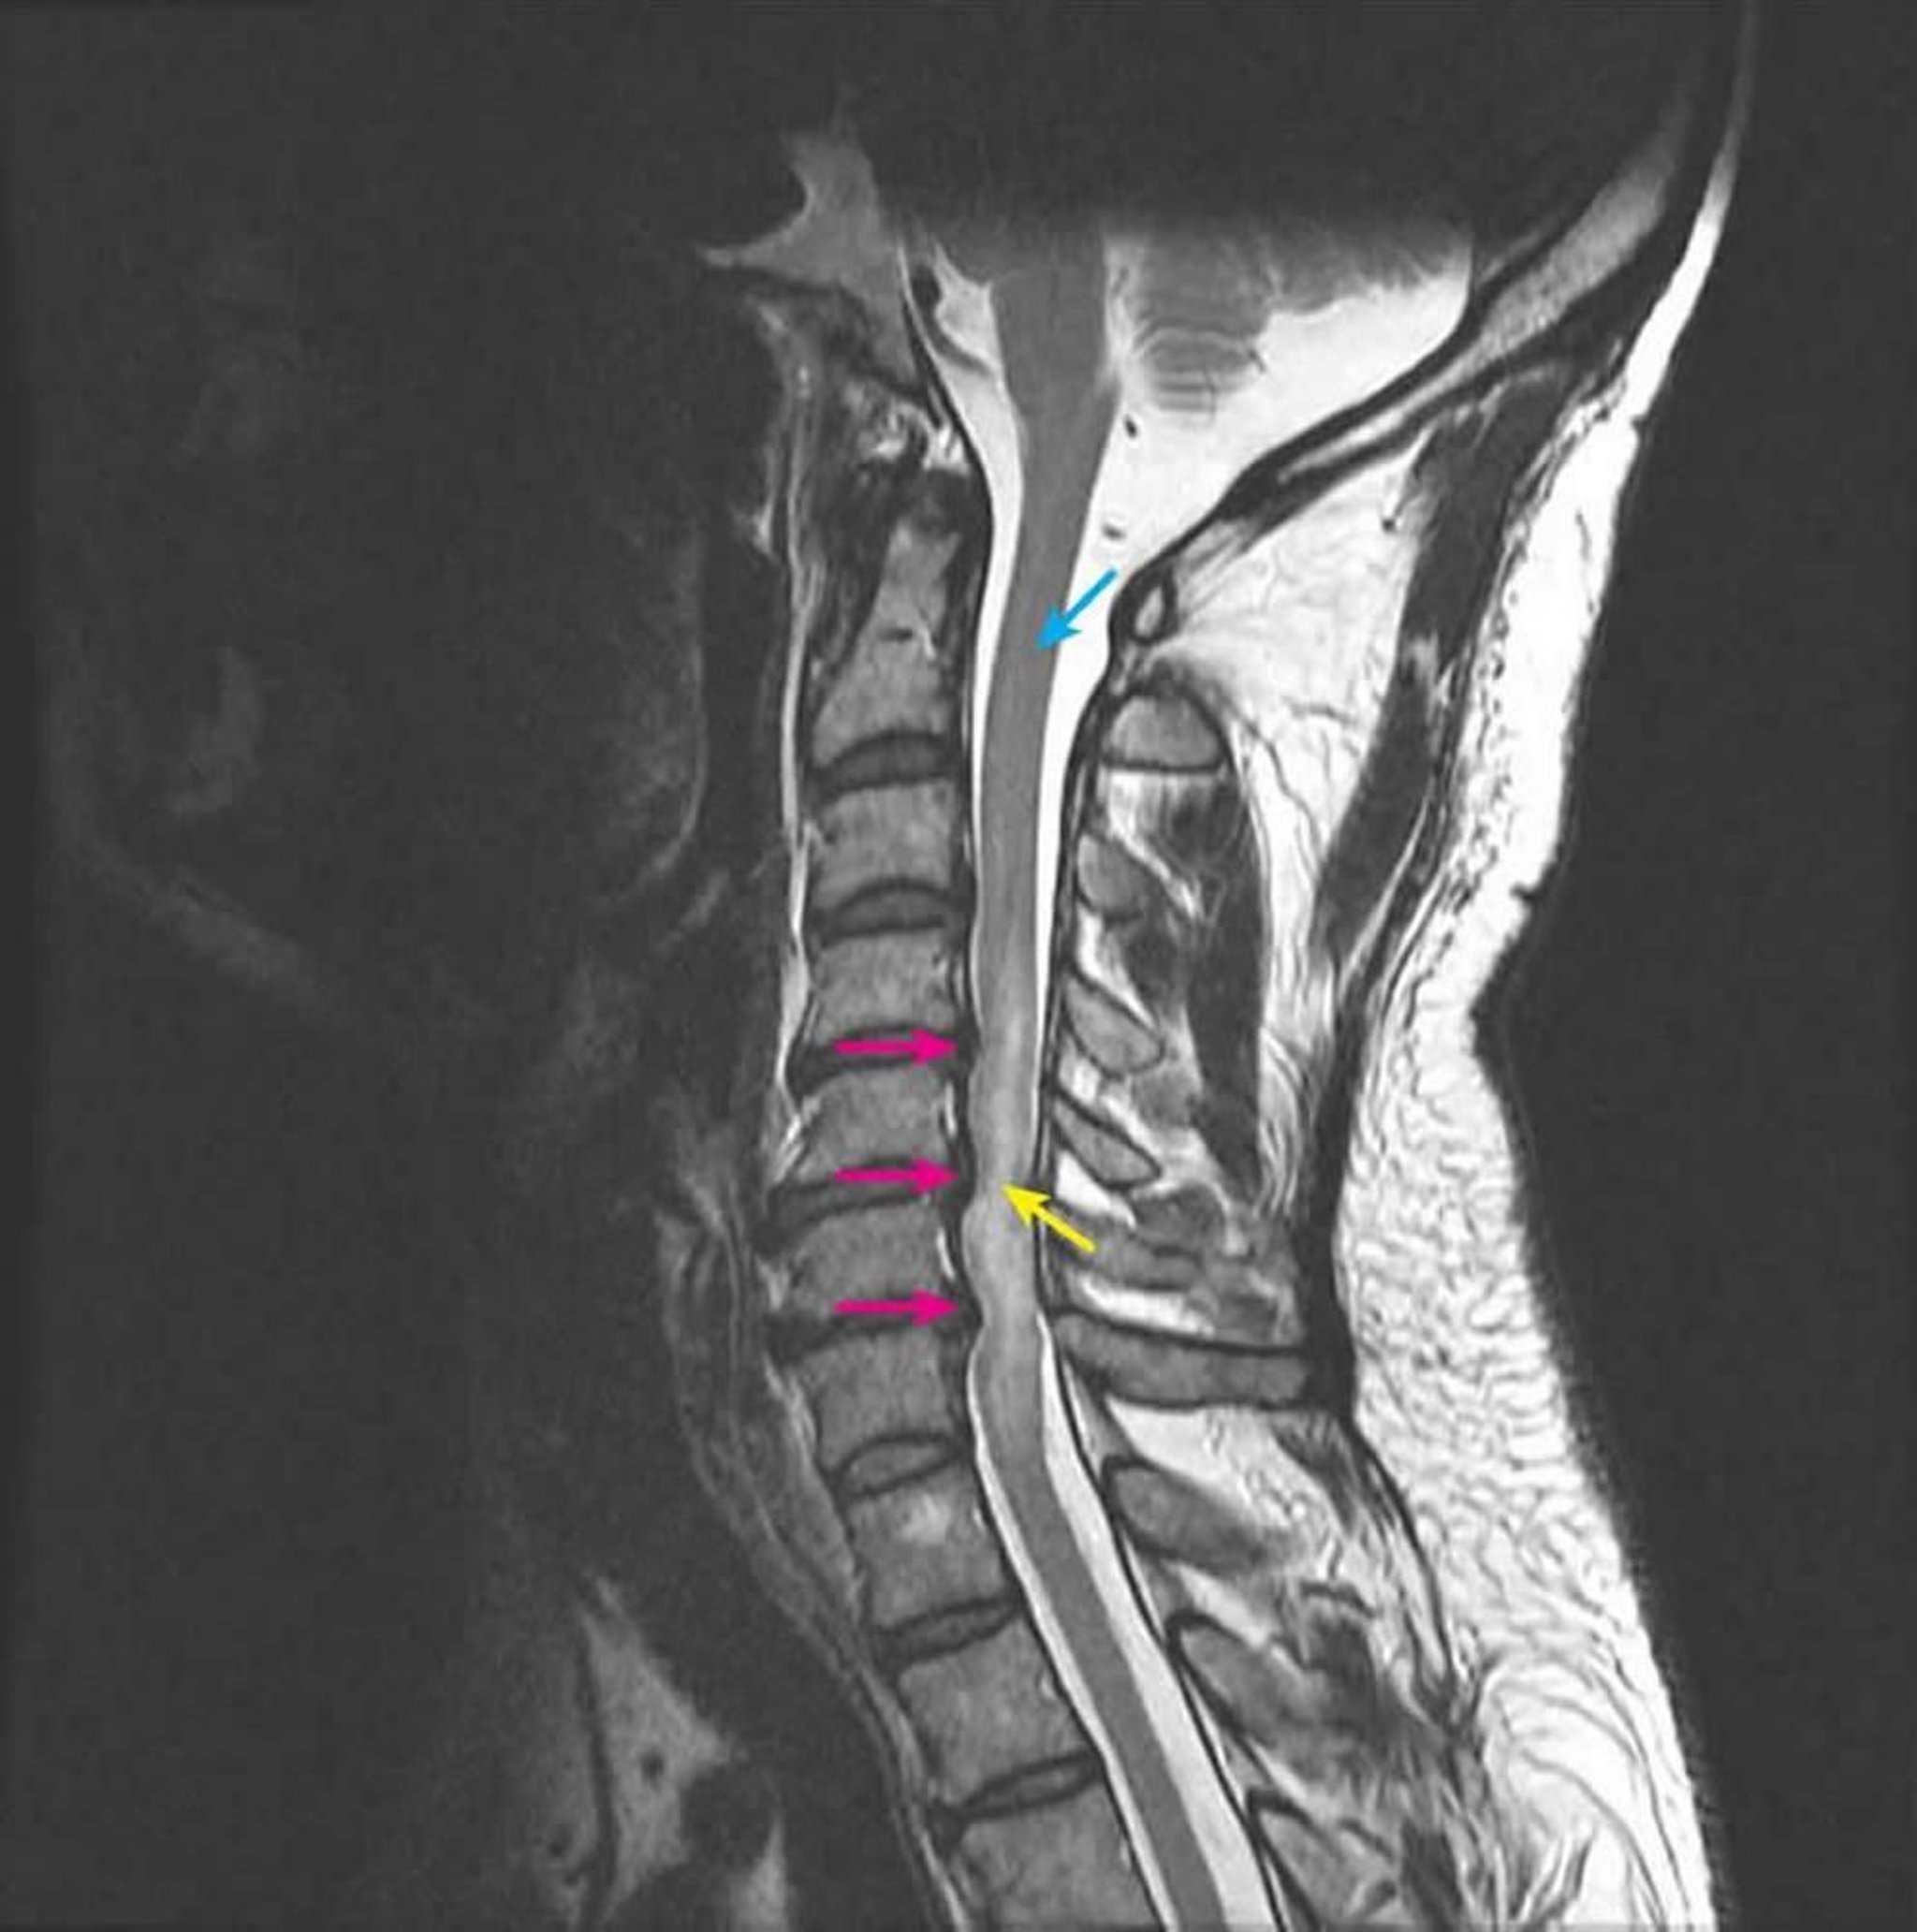

Myélopathie compressive

L'IRM sagittale pondérée en T2 montre une compression de la moelle épinière aux niveaux intervertébraux C4-5, C5-6 et C6-7 secondaires à des hernies discales postérieures à plusieurs niveaux (flèches roses). Le signal T2 intramédullaire est anormalement augmenté, ce qui représente un œdème de la moelle épinière (flèche jaune). Le signal normal de la moelle épinière est visible au niveau C2 (flèche bleue).

Courtesy of John Tsiouris, MD, Division of Neuroradiology, New York–Presbyterian Hospital/Weill Cornell Medical Center.